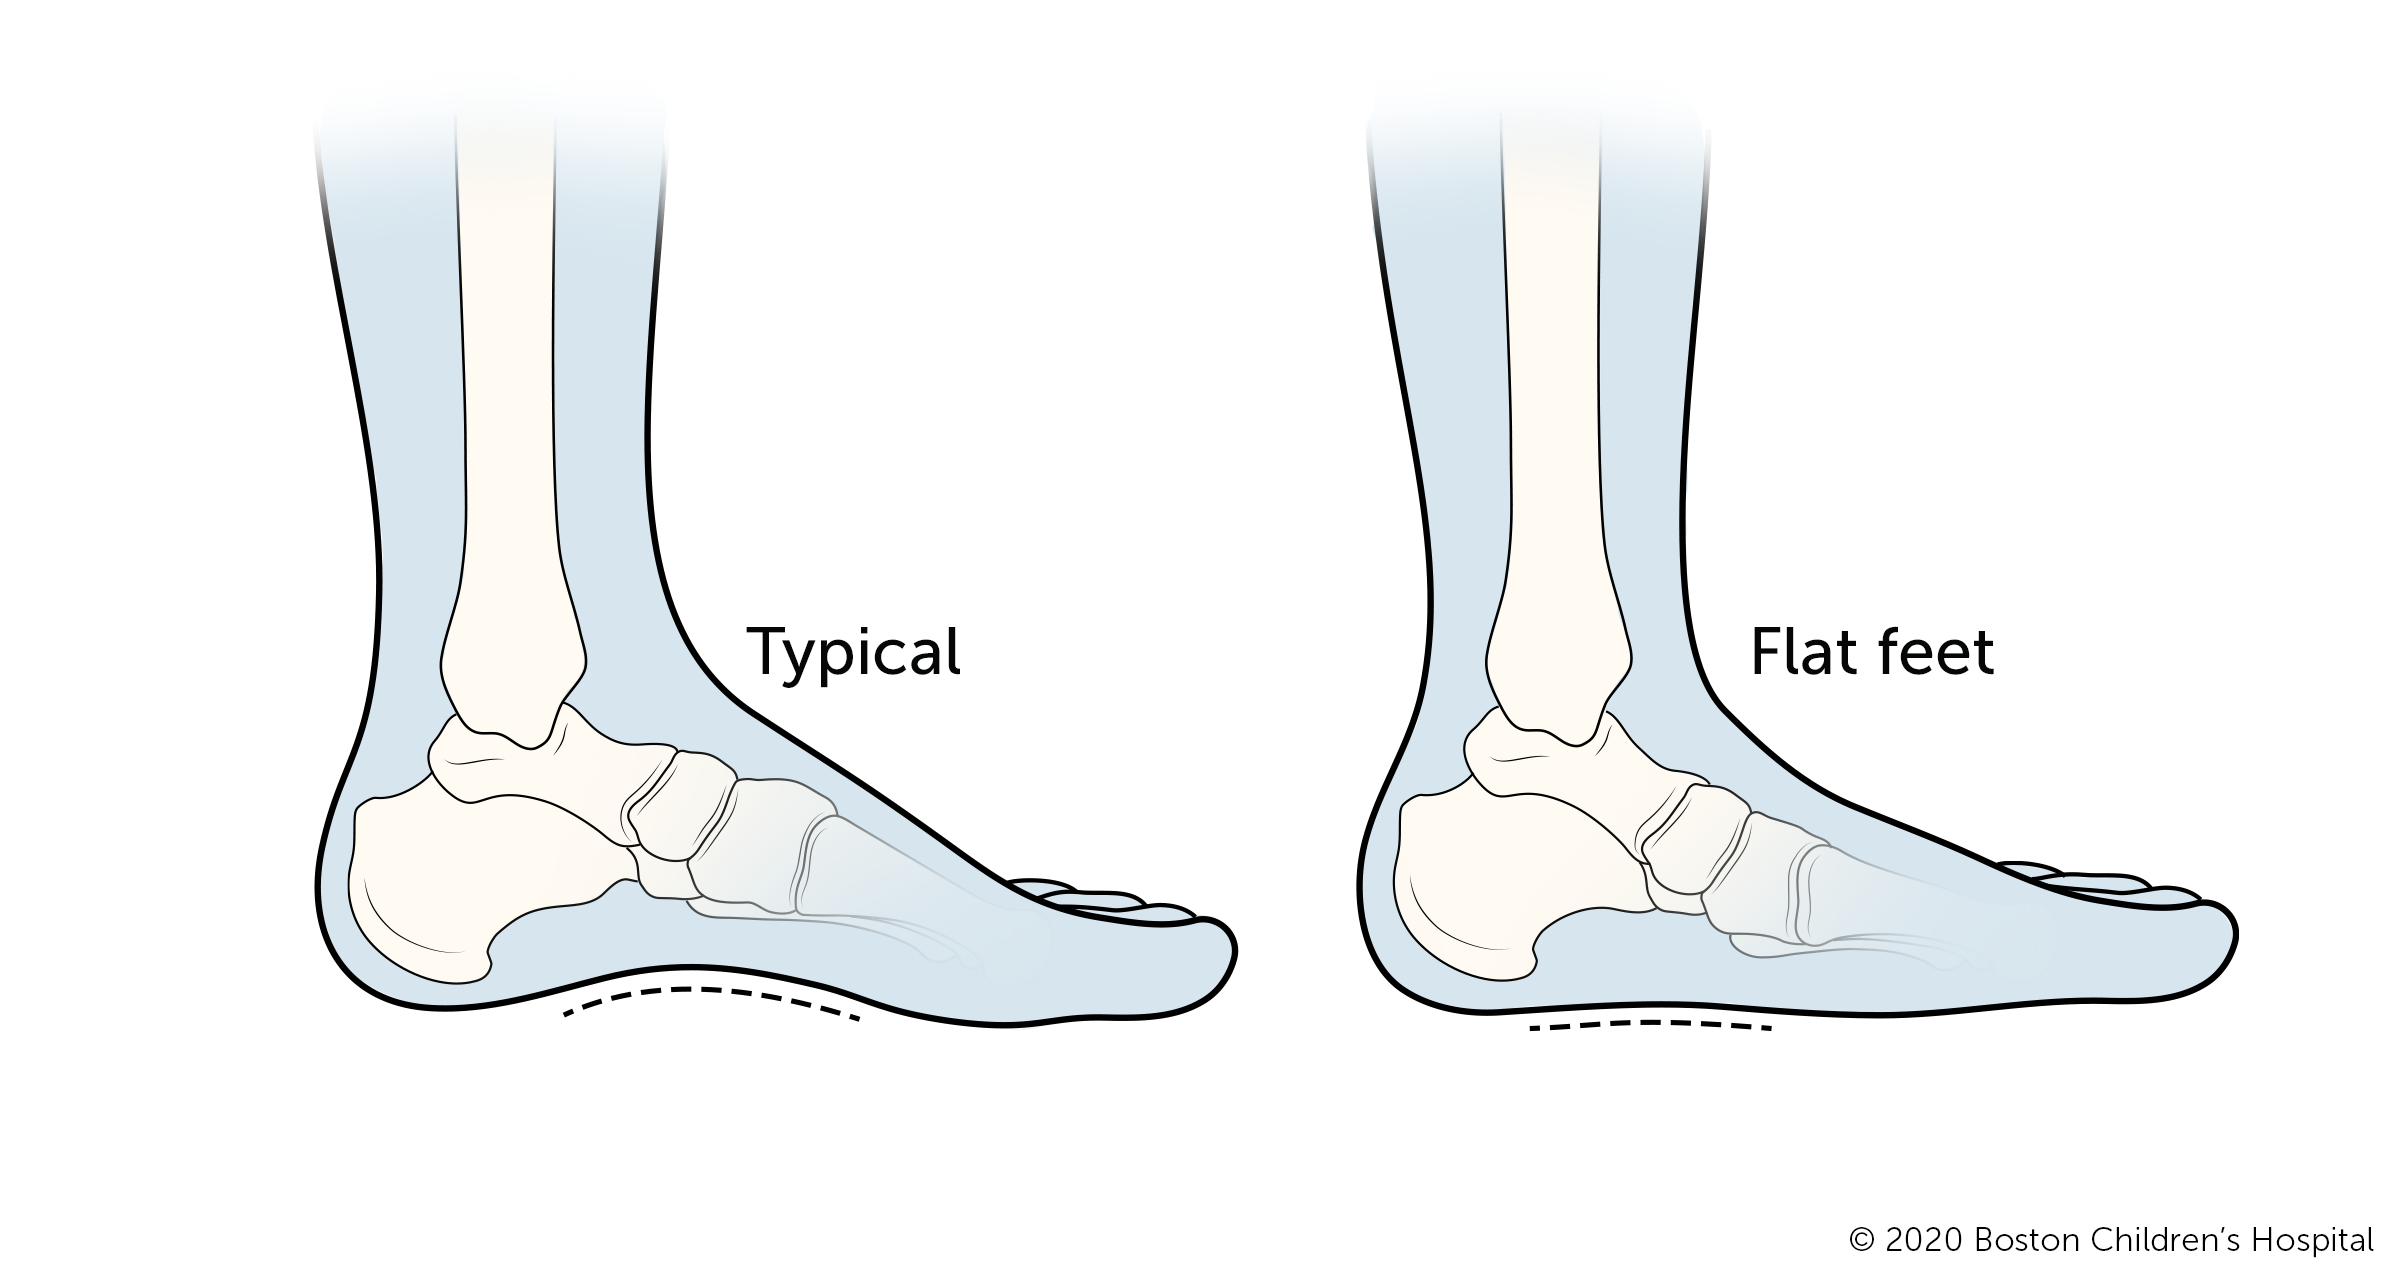

Flatfeet

Flatfeet are normal in infants and young children. Children have flat feet when the arches in their feet have not yet developed and their entire feet press against the floor. The arches develop throughout childhood until about age 10.